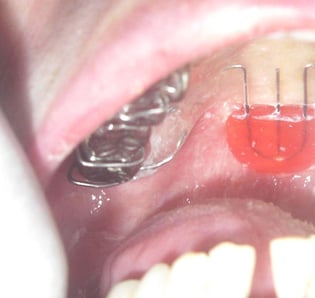

舌の動きが悪くて口腔内で真空状態を作ることが出来なければ、口の中の食べ物を喉に送り込むことはできません。そのようなケースで舌の間接訓練を行っても不十分な場合、舌接触補助床(PAP)と呼ばれる装置を用いることがあります。

また口の息が鼻に漏れてしまうやはり口の中の食べ物が喉に運ばれなくなります。そういった場合、軟口蓋挙上装置(パラタルリフト)やスピーチエイドといった装置を用いることがあります。